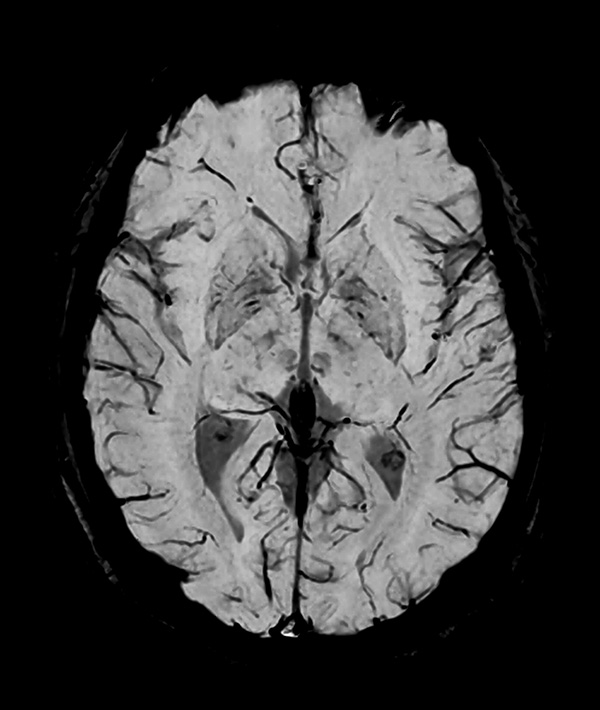

Comprehensive Brain imaging at 1.5T

Used Solution

• Clinical Application